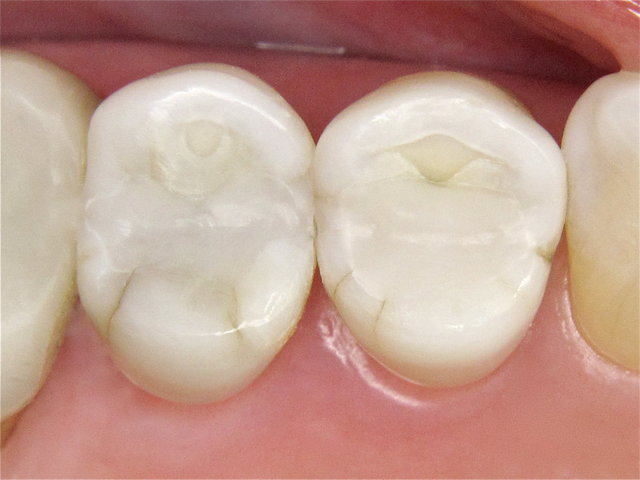

Alte undichte Amalgam-Füllungen mit Karies und Rissen ...

Composit-Füllungen by CLINICDENT ✓